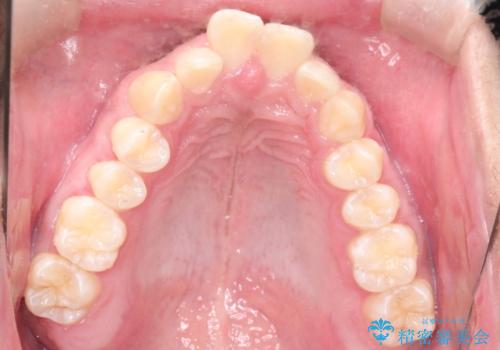

インビザラインによる出っ歯の矯正

- 出っ歯と下の歯のガタガタを主訴に来院されました。

上の奥歯を後方に移動させて、スペースを作り前歯を内側に引っ込める計画としました。

インビザラインによるマウスピース矯正で治療をすることとしました。